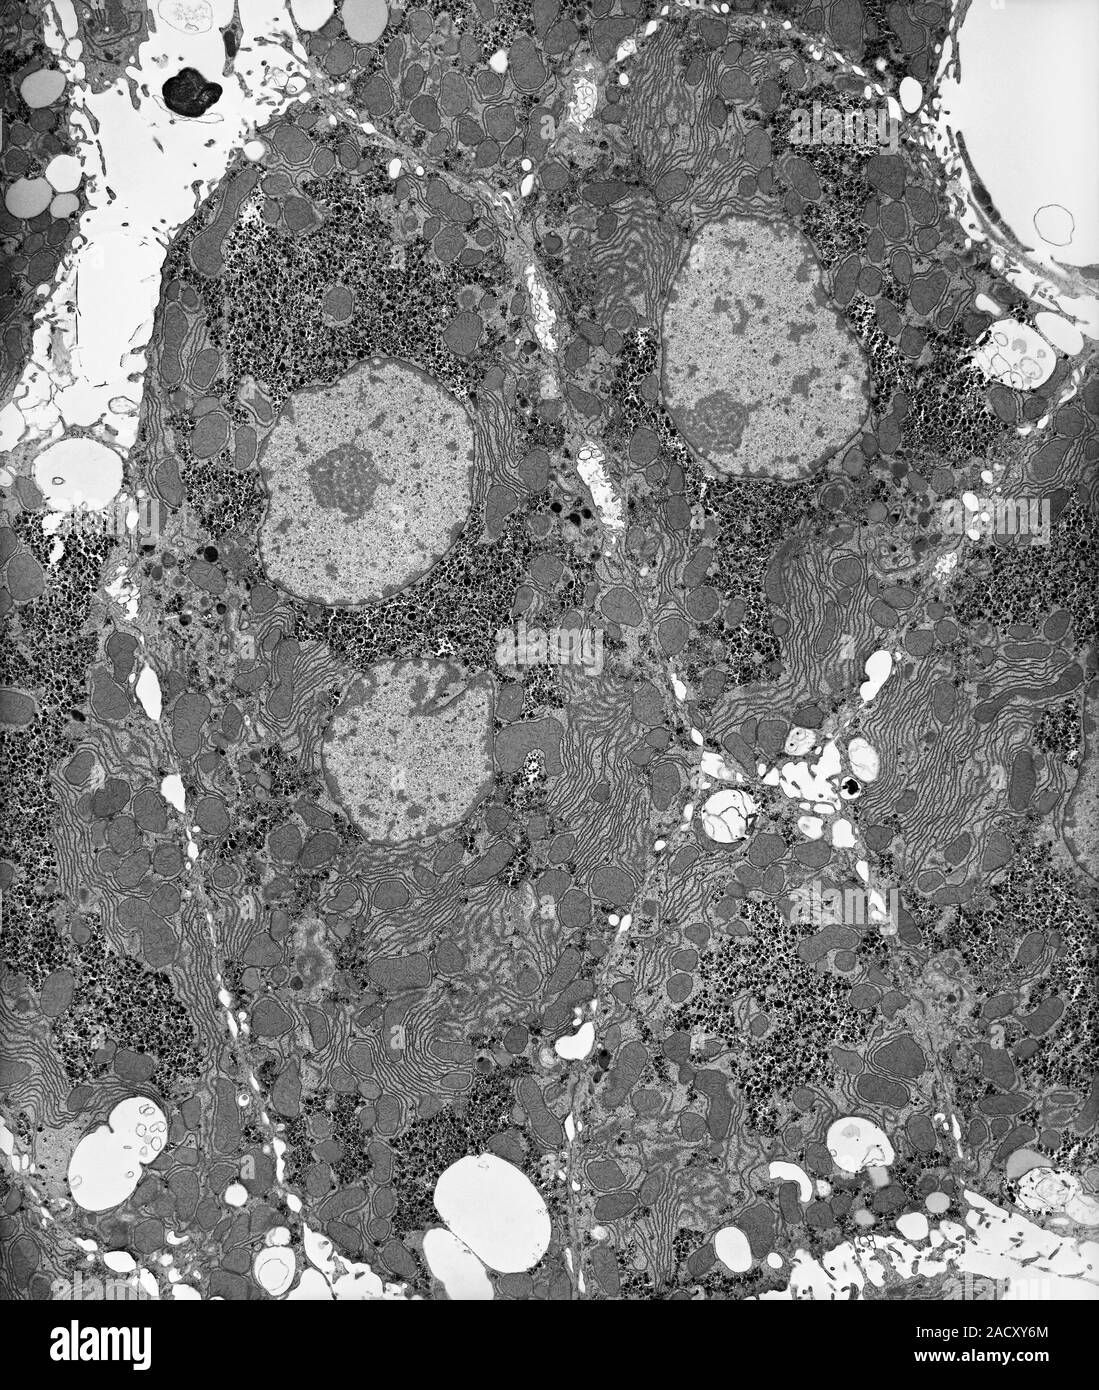

From www.alamy.com

Liver tissue hepatocytes. Transmission electron micrograph (TEM) of a section through liver Liver Glycogenated Nuclei glycogenated nuclei interface hepatitis defined as damage and progressive loss of hepatocytes at the interface of the lobular parenchyma. They are a normal finding in childhood,. liver biopsy is the gold standard for diagnosis of glycogenic hepatopathy, typical features are swollen hepatocytes, due to the. glycogenated nuclei optically appear as empty vacuoles on h&e stain (fig. . Liver Glycogenated Nuclei.